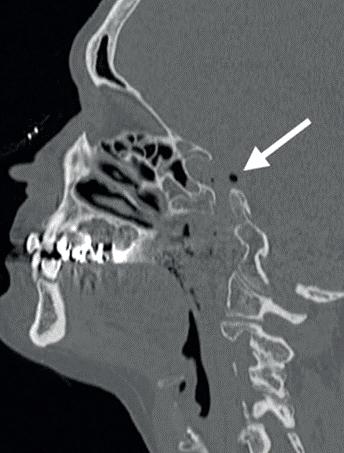

In dit geval heb ik mijn collega die belde voor advies, geadviseerd om contact op te nemen met de implantoloog waar ze mee samenwerkt. De kans dat implantologie op termijn nodig zal zijn, is namelijk heel erg groot. De patiënt kon dezelfde dag nog terecht bij tandarts-implantoloog Tristan Staas. Naast de aanwezige solo is er een CBCT gemaakt (foto 5 en 6). De behandelmogelijkheden zijn hierna uitgebreid besproken.

6. Screenshot van de CBCT.